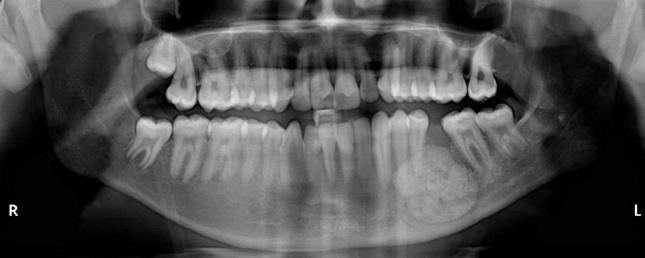

下颌骨骨样骨瘤:一例病例报告并文献复习

Osteoid osteoma of the mandible: A case report with review of the literature.

Osteoid osteoma is a benign skeletal neoplasm most frequently observed in young individuals. The tumor most commonly occurs in the femur, the tibia, and the phalanges; however, jaw lesions are very rare. Herein, we report a rare case of osteoid osteoma that presented in the mandible of a 20-year-old boy. This report also reviews the cases of osteoid osteomas of the jaws that have been reported in the English literature so far.

摘要

骨样骨瘤是一种良性骨肿瘤,最常见于年轻人。该肿瘤最常发生于股骨、胫骨和指骨;然而,颌骨病变非常罕见。在此,我们报告一例罕见的骨样骨瘤病例,发生在一名20岁男孩的下颌骨。本报告还回顾了迄今为止英文文献中报道的颌骨骨样骨瘤病例。